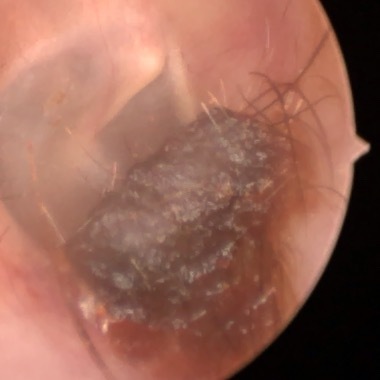

Cholesteatoma Clinical

Ear Canal